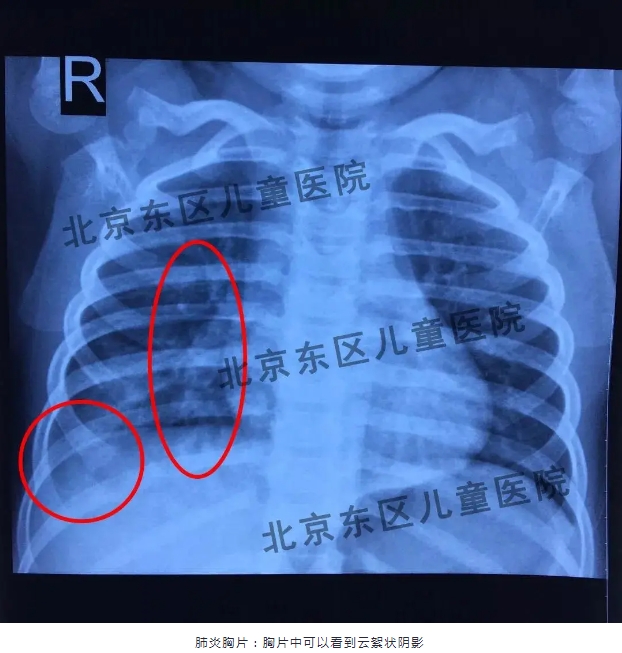

从目前临床来看,今年的肺炎支原体较去年相比还是有些变化的,今年的特点主要表现为孩子的症状不典型,有些孩子既发烧又咳嗽;有些孩子是只高烧,但是一开始不咳嗽,在3-4天后才出现咳嗽的表现。还有些孩子听着肺里也没事儿,咳嗽3天,也不发烧,一拍片子已经是肺炎了,所以很多家长都不太理解,这主要是因为支原体肺炎早期病变是在肺间质,所以往往听诊听不到啰音,但并不代表孩子没有肺炎。所以提醒家长们要注意如果孩子持续发烧超过三天,不管有没有咳嗽或者只是剧烈的咳嗽,不发烧的情况,一定要去医院请医生评估一下是感冒、支气管炎还是肺炎,千万不要在家扛着,以免延误病情。

没什么表现 怎么就肺炎了?

肺炎听得见、看得见吗?

很多家长可能遇到过这种情况:孩子发烧咳嗽到医院看病,医生听诊后说肺部没什么问题,但是过了几天病情没有好转再到医院检查就变成肺炎了,家长就对医生的听诊水平产生了质疑。